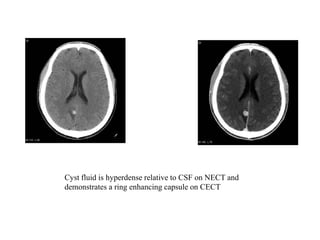

Cyst fluid is hyperdense relative to CSF on NECT and

demonstrates a ring enhancing capsule on CECT

Colloidal vesicular • Cystfluid becomes turbid – CT: hyperattenuating to CSF – MRI T1: hyperintense to CSF • Surrounding oedema • Cyst and the wall become thickened and brightly enhances • Scolex can often still be seen as an eccentric focus of enhancement

Cyst fluid ishyperdense relative to CSF on NECT and demonstrates a ring enhancing capsule on CECT